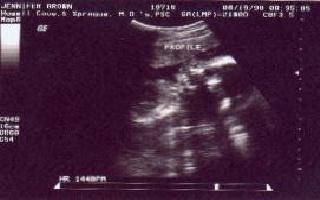

You might have a hard time making out the picture if you look to your right , you should be able to see a head. The picture is a side view of her face. You can see the curve of her forehead that leads to her nose, down to where her lips are and stops with her chin. The dark circle close to the nose is her eye.